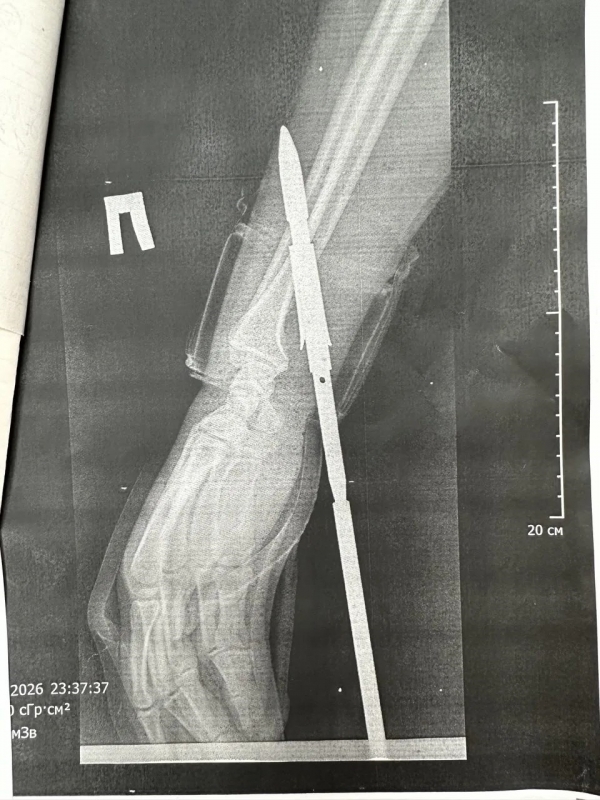

В ГАУЗ «ГБ» г. Орска рассказали, что гарпун с двумя зубцами прошёл между костями, не задев их.

Специалисты извлекли инородное тело, обработали рану и оказали пациенту всю необходимую помощь.